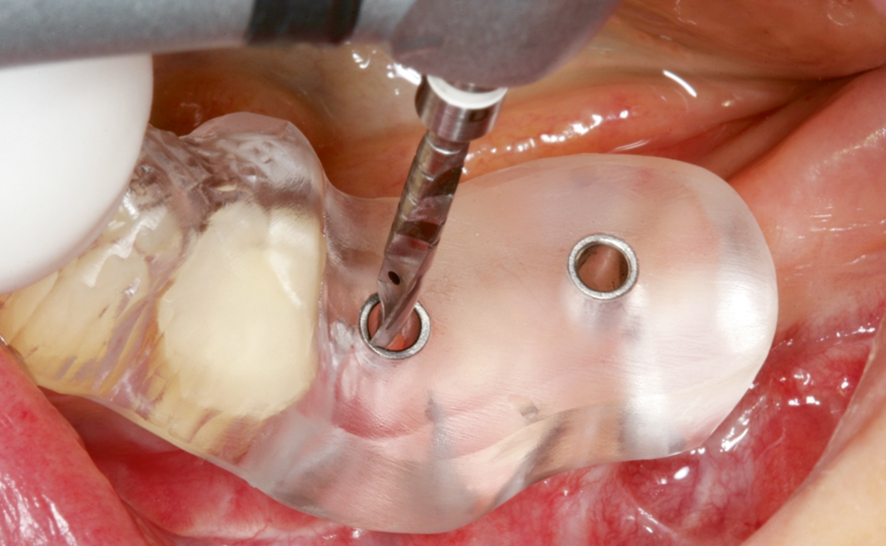

セレックガイドの作製を行います。

セレックガイドにてインプラントの埋入位置を決めます。

ワイズデンタルクリニックでは従来のインプラント治療に加え、デジタルスキャナーとCTデータをもとにサージカルガイドを作成しインプラント手術を行っております。

CTデータとデジタルスキャナーのデータをリンクさせて、セレックシステムでアウトプットしたサージカルガイドを用います。CTデータ・スキャンデータからのシミュレーションを行うことにより、治療の安全性が期待されます。